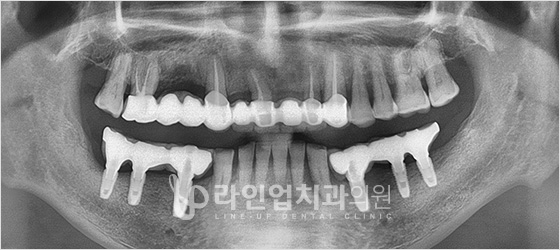

치료전

Before

치료후

After

아래 어금니 임플란트 (59세/남/ 2015.07.08~2016.02.04)